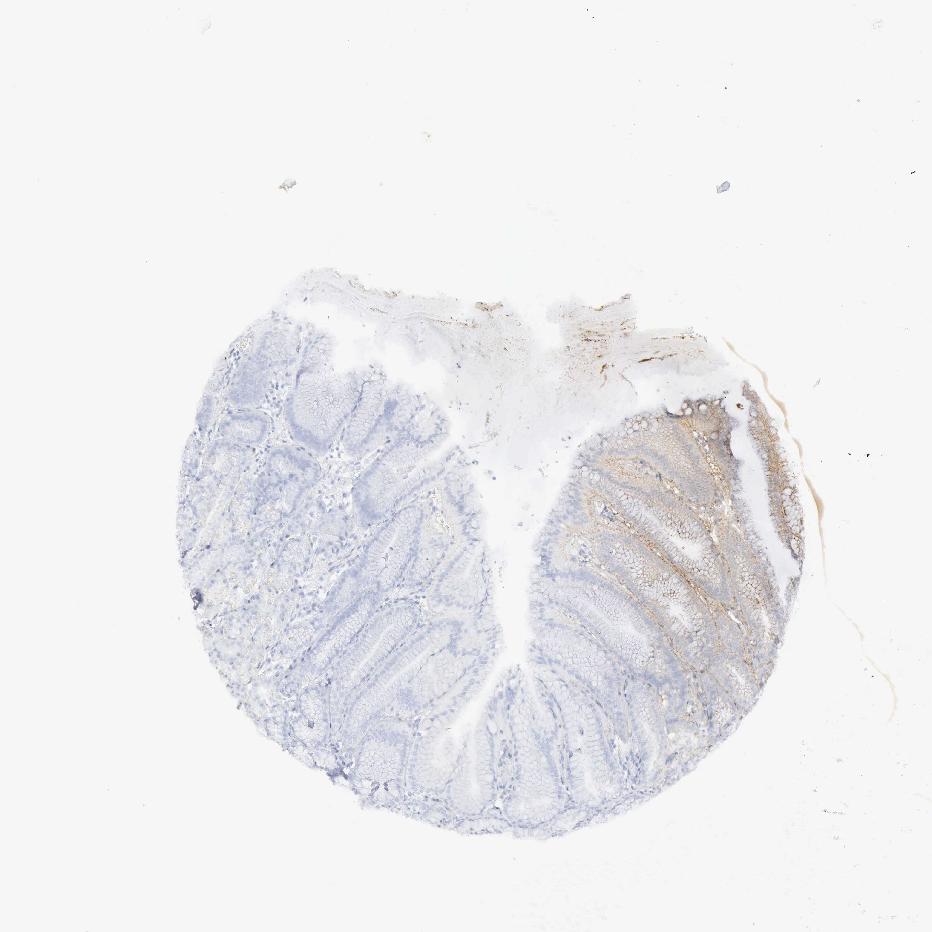

STOMACH 1 - Antibody stainingi

Antibody staining in the annotated cell types in the current human tissue is reported as not detected, low, medium, or high, based on conventional immunohistochemistry profiling in selected tissues. This score is based on the combination of the staining intensity and fraction of stained cells.

Each image is clickable and will lead to virtual microscopy that enables deeper exploration of all samples and also displays staining intensity scores, fraction scores and subcellular localization as well as patient and tissue information for each sample.

Antibody HPA001097

Glandular cells High

STOMACH 2 - Antibody stainingi

Glandular cells Medium